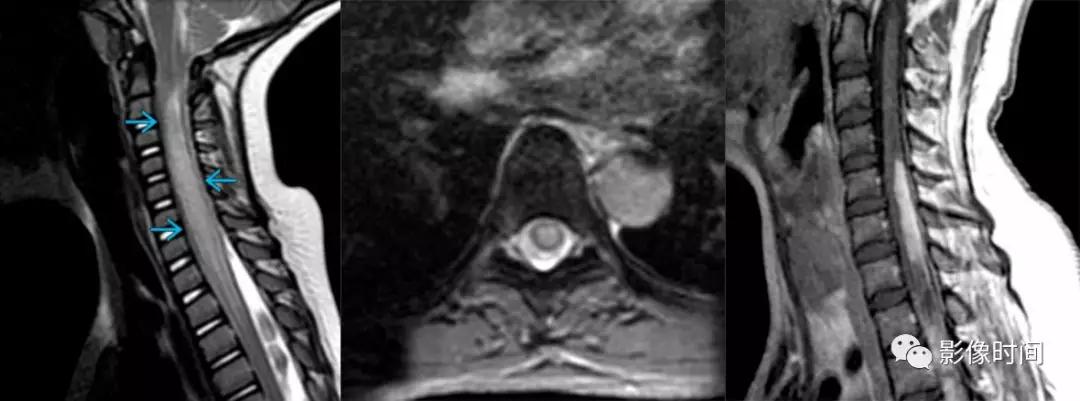

脊髓灰质炎(poliomyelitis):是由脊髓灰质炎病毒引起的脊髓前角运动神经元损害为主,患者多为 1-6 岁儿童。

MRI:

-

双侧灰质前角对称性 T2WI 高信号,类似于脊髓前动脉梗死的「鹰眼征」

急性期明显强化

T2WI双侧灰质前角对称结节状高信号,似「鹰眼」

结节病(sarcoidosis):是一种系统性肉芽肿疾病,多器官存在非干酪性肉芽肿为主,累及中枢神经系统发病率为 14%–27% ,小于 10%CNS 结节病患者有脊髓病变。

颈髓>胸髓

髓内长节段 T2WI 高信号(提示血管周围渗出)

脊髓表面多发结节状强化

颅内脑膜、脊膜多发强化(线样、结节状)

骨质异常强化

模式图显示脊髓内多发片状炎性渗出,T2WI 显示脊髓内长节段高信号,增强扫描椎体出现结节状强化出现多发结节状高信号